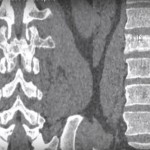

Paget’s Disease Vs Metastatic Prostate Tumours!

Courtesy: Prof Nabil Ebraheim, University of Toledo, Ohio, USA